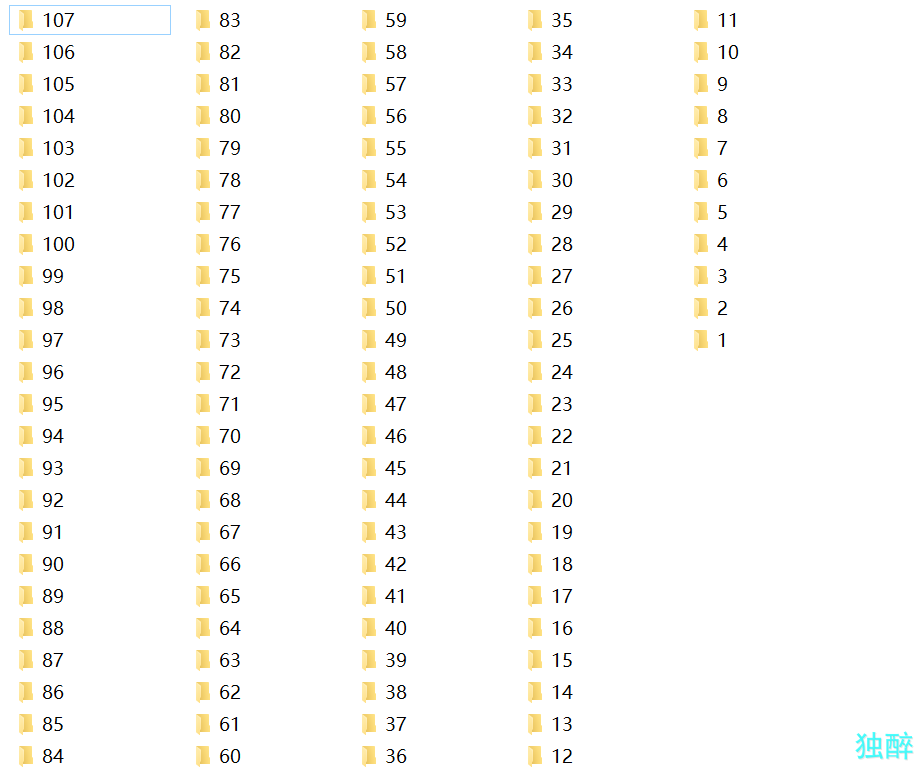

每个病人一个文件夹

每个病人一个文件夹